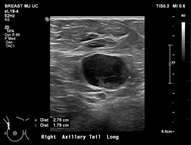

Case: Axillary Lymphadenopathy  Figure 2

Figure 2. Ultrasound showing benign left axillary lymph node with cortical thickness less than 3mm and preserved fatty hilum.

Ultrasound is the best modality for characterizing lymph nodes allowing for evaluation of shape, cortical thickness and presence or absence of fatty hilum. On ultrasound, normal axillary lymph nodes have an oval or lobulated shape with a preserved fatty hilum and cortical thickness less than 3 mm (figure 2). The echogenic hilum has arterial flow which can be assessed using color doppler imaging.